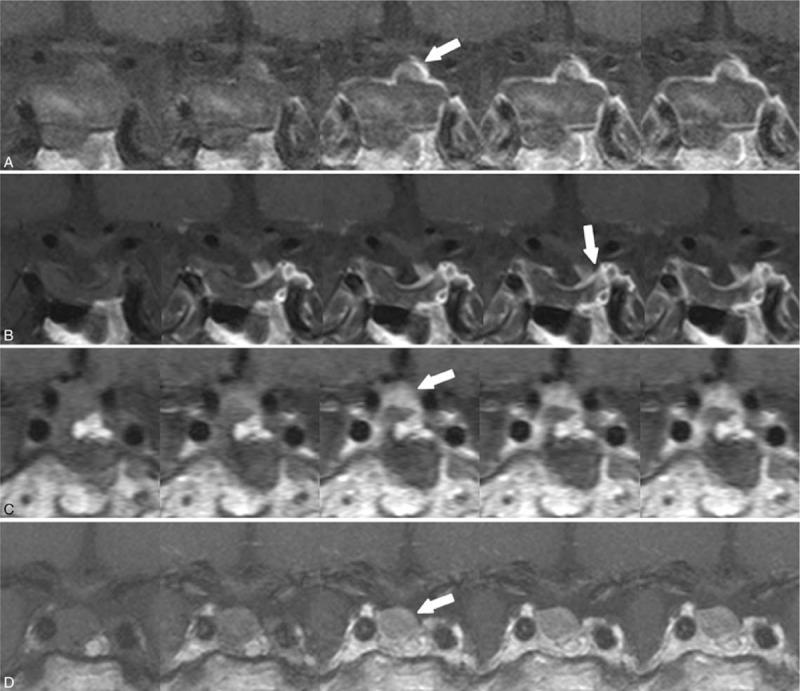

To establish magnetic resonance imaging (MRI) features that differentiate residual tumors from postoperative surgical changes following the transsphenoidal approach of a pituitary adenoma.We analyzed residual enhancements at the tumor bed in 52 patients who underwent dynamic contrast-enhanced sella MRI within 48 hours after surgery and at 6 to 28 months. Patients were divided into 2 groups defined by either peripheral or nodular enhancement patterns. For each group, we measured the maximum thickness of the residual enhancing portion and compared differences in the residual tumor and postoperative changes.Among the tumors examined in the 52 patients, 19 residual tumors showed nodular (n = 16) and peripheral (n = 3) enhancement patterns, and 33 postoperative changes showed nodular (n = 3) and peripheral (n = 30) enhancement patterns. The mean residual tumor thickness was 7.1 mm (range, 2.9-16.8 mm) and 1.9 mm (range, 1.0-7.4 mm) in the postoperative change. Receiver operating characteristic curve analysis revealed that a 3.9-mm thickness was associated with 89% sensitivity, 97% specificity, and 94% accuracy for diagnosis of residual tumor.On immediate postoperative MRI, residual enhancement with greater than 3.9-mm thickness and nodular pattern suggest residual pituitary adenoma tumor.

为确定垂体腺瘤经蝶窦入路术后区分残留肿瘤与手术改变的磁共振成像(MRI)特征。我们分析了52例患者肿瘤床的残留强化情况,这些患者在术后48小时内及术后6至28个月接受了动态对比增强鞍区MRI检查。患者根据外周或结节状强化模式分为两组。对于每组,我们测量了残留强化部分的最大厚度,并比较了残留肿瘤与术后改变的差异。在52例患者检查的肿瘤中,19例残留肿瘤表现为结节状(n = 16)和外周(n = 3)强化模式,33例术后改变表现为结节状(n = 3)和外周(n = 30)强化模式。残留肿瘤的平均厚度为7.1mm(范围2.9 - 16.8mm),术后改变的平均厚度为1.9mm(范围1.0 - 7.4mm)。受试者工作特征曲线分析显示,厚度3.9mm对残留肿瘤诊断的敏感性为89%,特异性为97%,准确性为94%。术后即刻MRI上,厚度大于3.9mm且呈结节状模式的残留强化提示残留垂体腺瘤肿瘤。